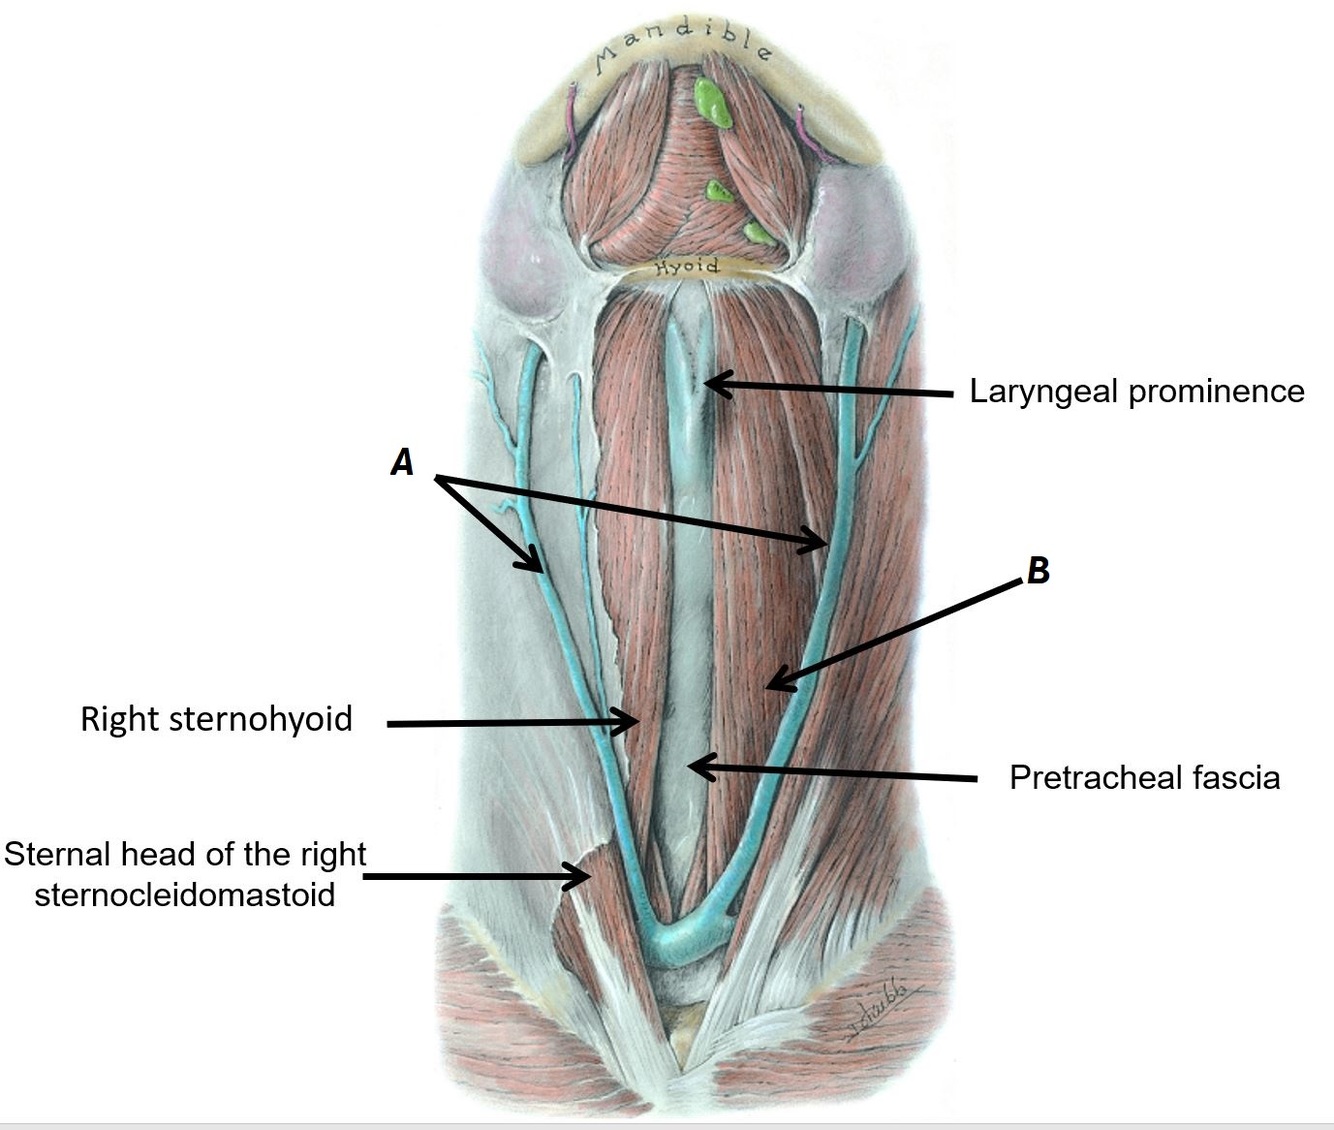

Name structures A, B and C

A - Sternal head of right sternocleidomastoid

B - Right sternohyoid muscle

C - Pretracheal fascia